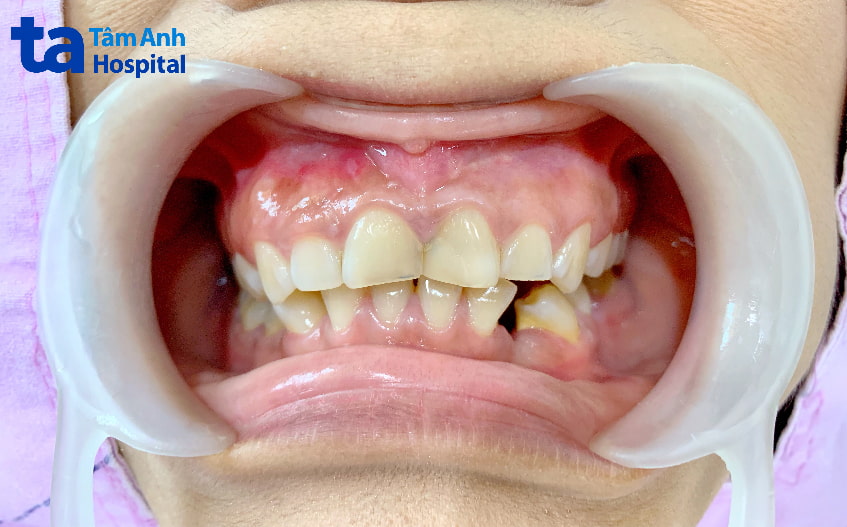

Sai lệch khớp cắn chéo được nhận biết rõ ràng khi quan sát vùng răng cửa, nhưng lại không biểu hiện nhiều trên khuôn mặt. Đặc biệt, đối với những người có mức độ sai lệch khớp cắn nhẹ hoặc thuộc loại khớp cắn chéo phía sau, người đối diện sẽ rất khó nhận ra. Chỉ khi họ cười, mới có một số biểu hiện trên răng làm cho cung hàm trở nên kém tự nhiên và làm giảm thẩm mỹ khuôn mặt.

Khớp cắn chéo là hiện tượng các răng trên cung hàm không đồng đều, mà chia thành các nhóm khác nhau, một số chìa ra ngoài, trong khi một số khác cụp vào trong.

Khớp cắn chéo phía trước là tình trạng một số răng cửa hàm trên nằm sau răng cửa hàm dưới, trong khi một số răng cửa hàm trên khác lại nằm trước răng cửa hàm dưới. Khớp cắn chéo phía trước chiếm khoảng 4-5% dân số, tương tự như tình trạng móm nhưng ở mức độ nhẹ hơn, nên khó nhận biết và thường bị nhầm lẫn với khớp cắn sâu. Để phân biệt, nếu toàn bộ nhóm răng cửa hàm trên đều nằm sau răng cửa hàm dưới thì đó là khớp cắn sâu. Ngược lại, nếu răng cửa có cái thò cái thụt thì đó là khớp cắn chéo.